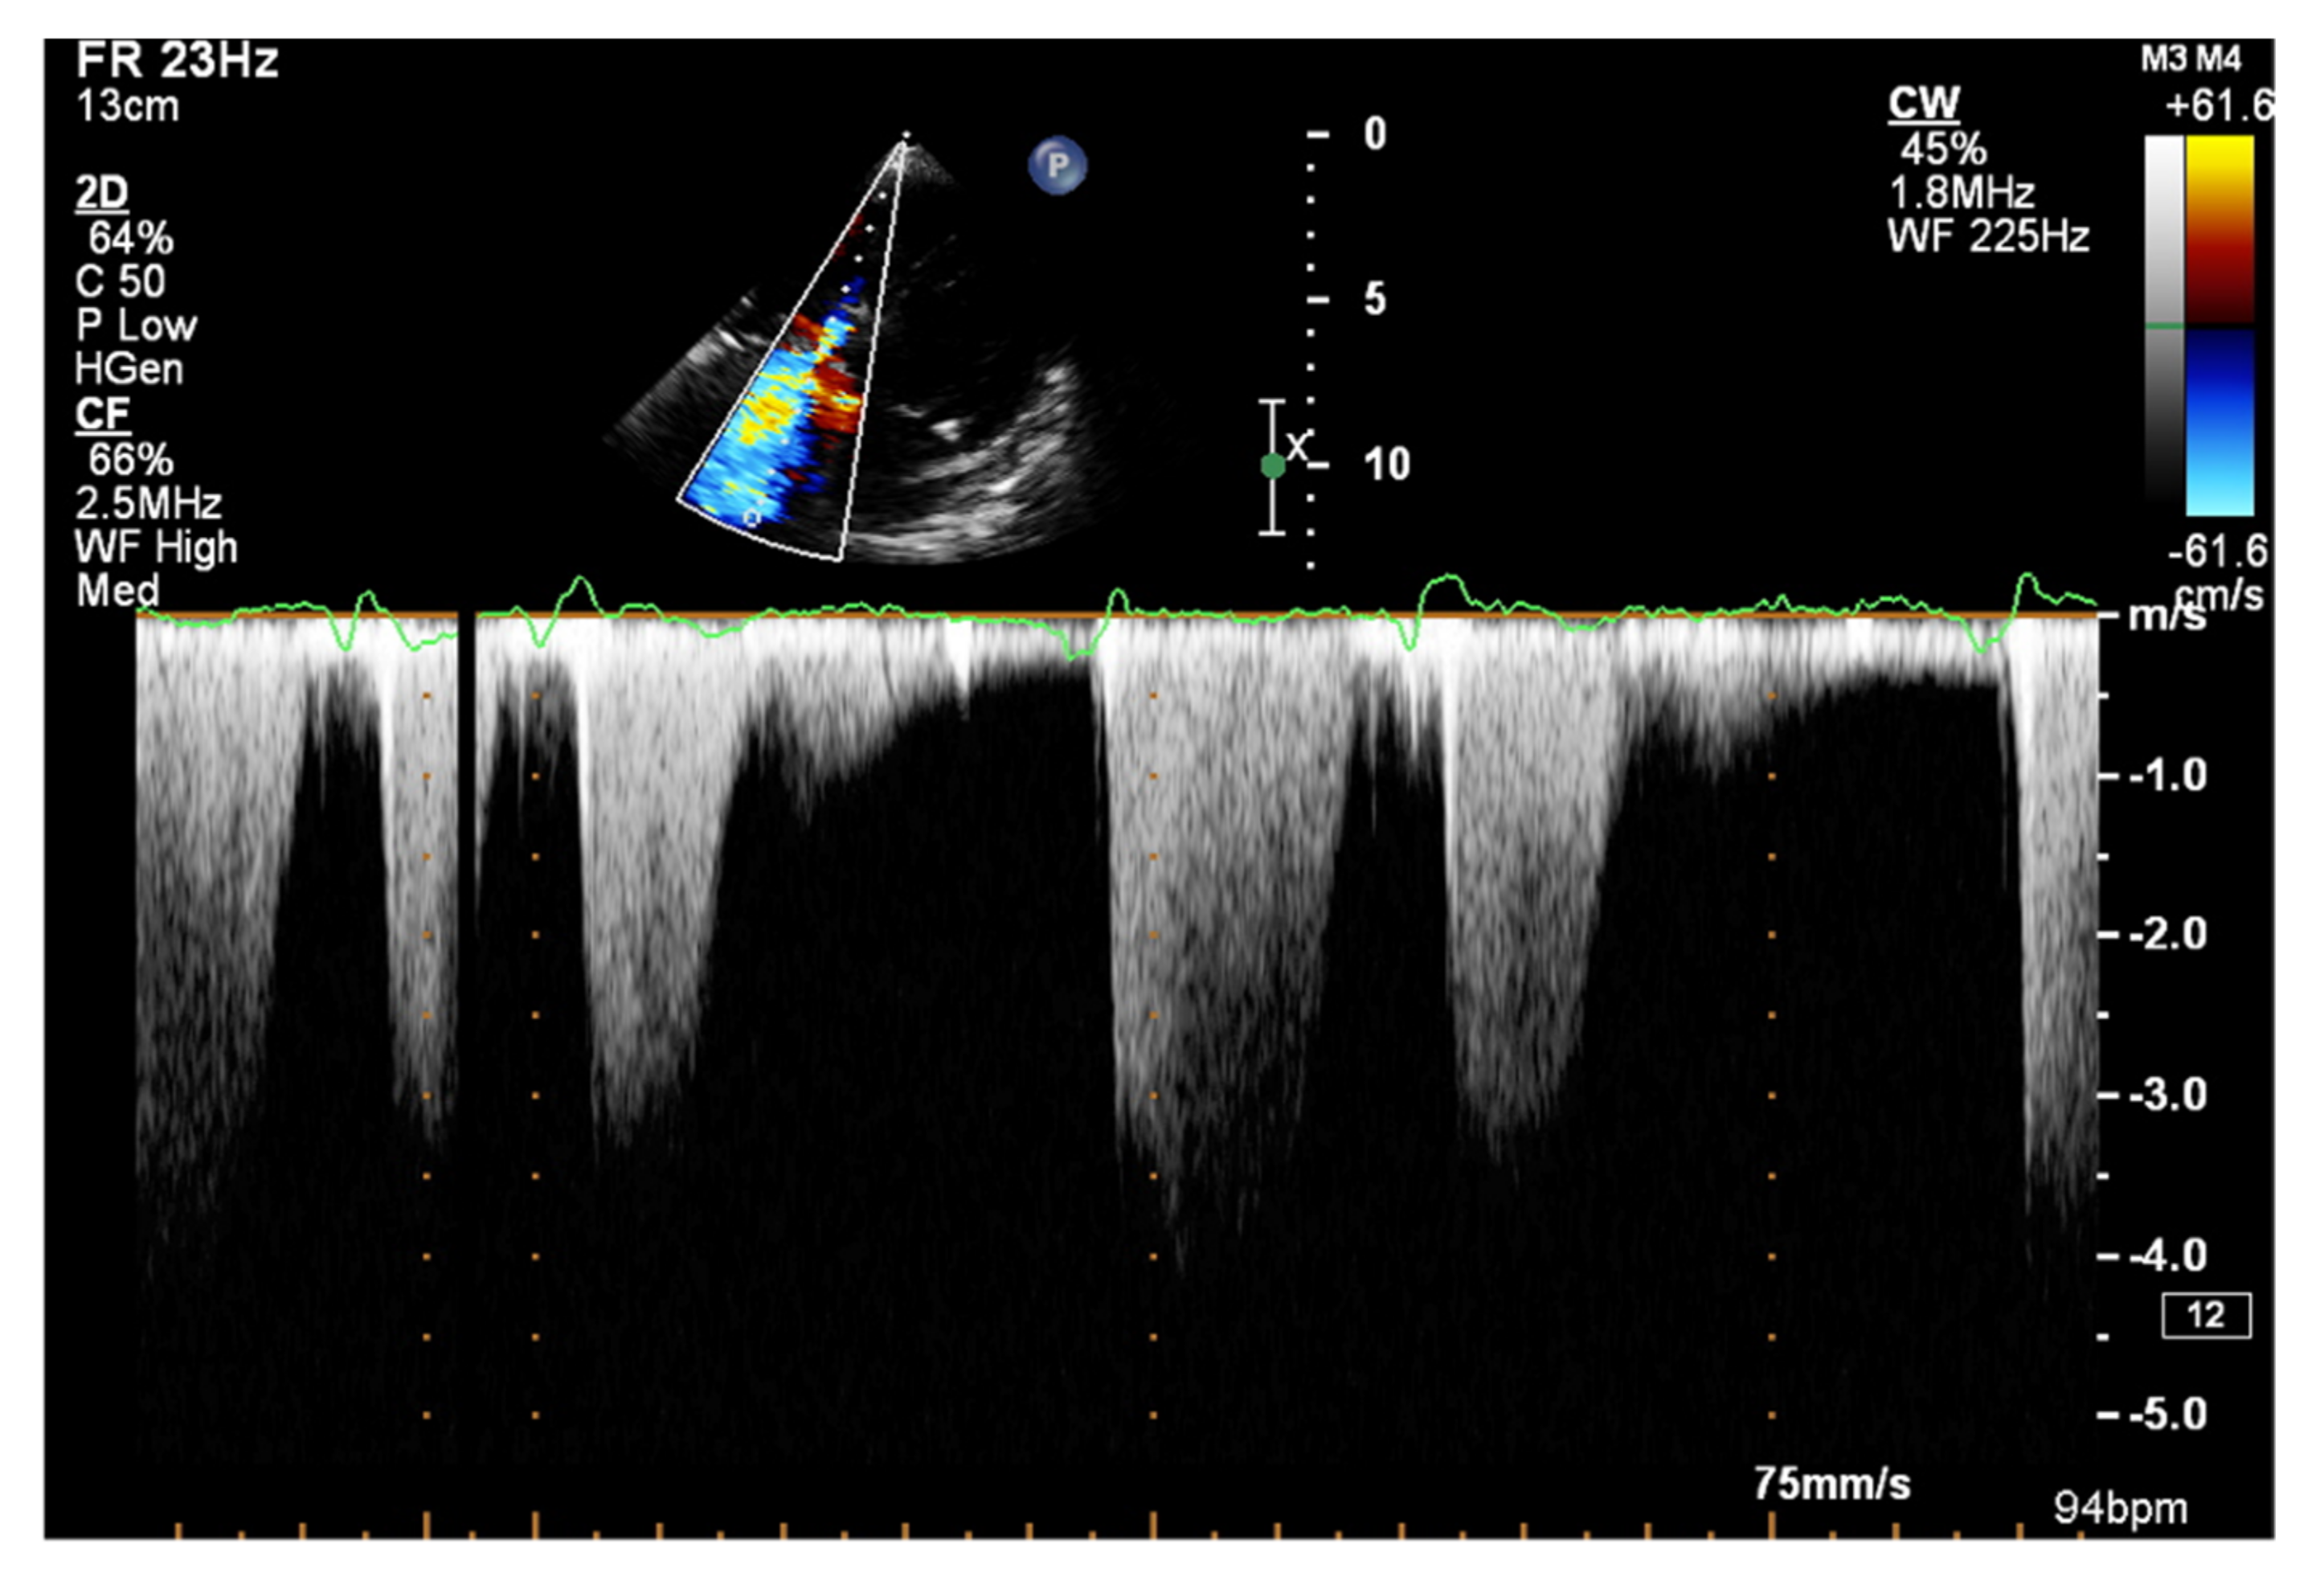

The dP/dt parameter, an indicator of the rate of pressure rise during the systolic phase in the RV, has a documented value in assessing RV systolic function [49]. To measure the dP/dt parameter, it is necessary to visualize a clear contour of the tricuspid return wave using the continuous wave Doppler (CWD). Singbal et al. showed that the dP/dt ratio correlates strongly with RVEF measured by CMR. Values of dP/dt below 400 mmHg/s were consistent with reduced RVEF [50]. In addition, decreased dP/dt is a significant TAPSE-independent marker of an adverse course of PAH and CTEPH [51].

Figure 12.

Doppler assessment of tricuspid regurgitant velocity (TRV). TTE, 4CH view. TTE: transthoracic echocardiography; 4CH: four-chamber.